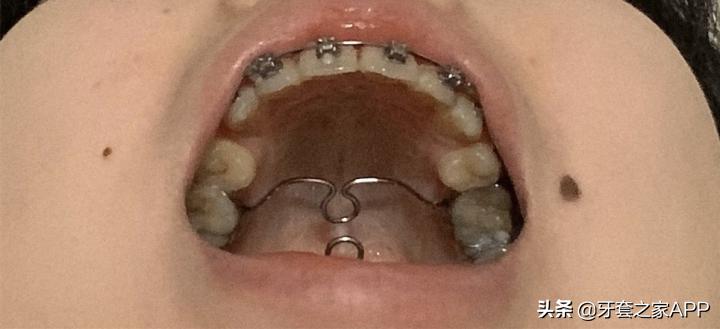

▲刚戴牙套

▲现在戴了两个横颚杆

医生说是为了让我的下巴更出来一点?刚戴上的时候真的巨痛苦,一直干呕,就像小时候看医生,医生用小木板压着你的舌头的感觉

现在适应了,没什么特别的感觉了,就是讲话很大舌头,咬字不清楚,然后吃青菜或者太大块的肉很容易挂在上面………